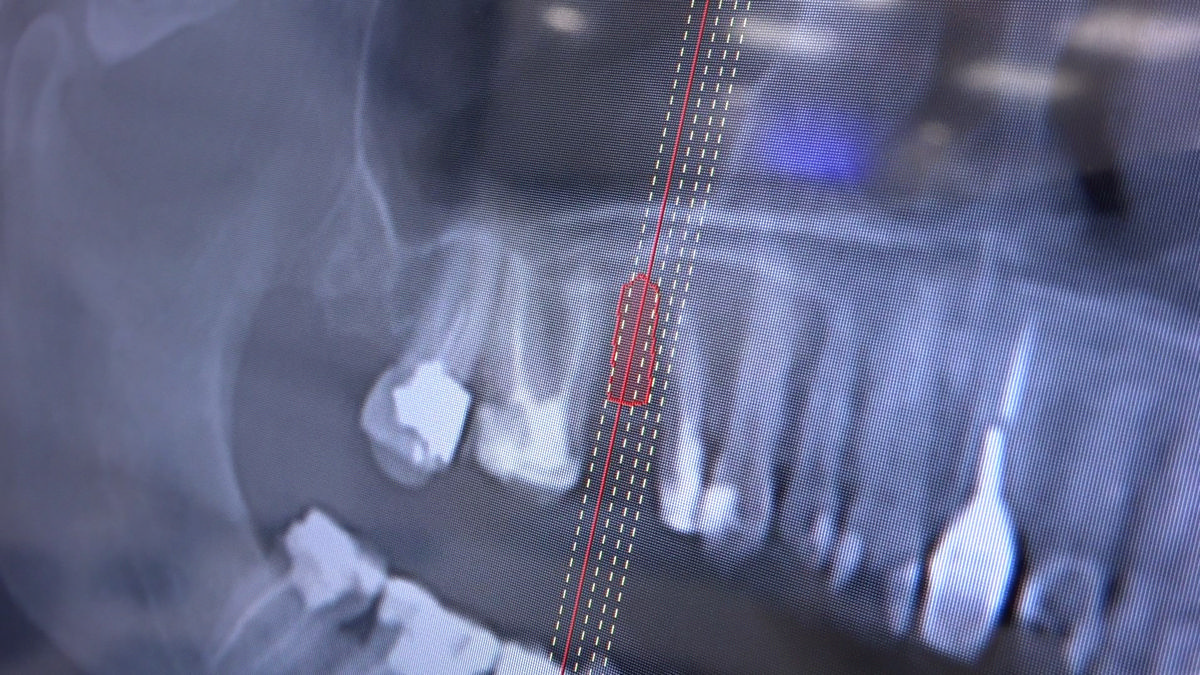

PRACTICULUM IMPLANTOLOGII - SEZON X - SESJA 4 - GRUPA B